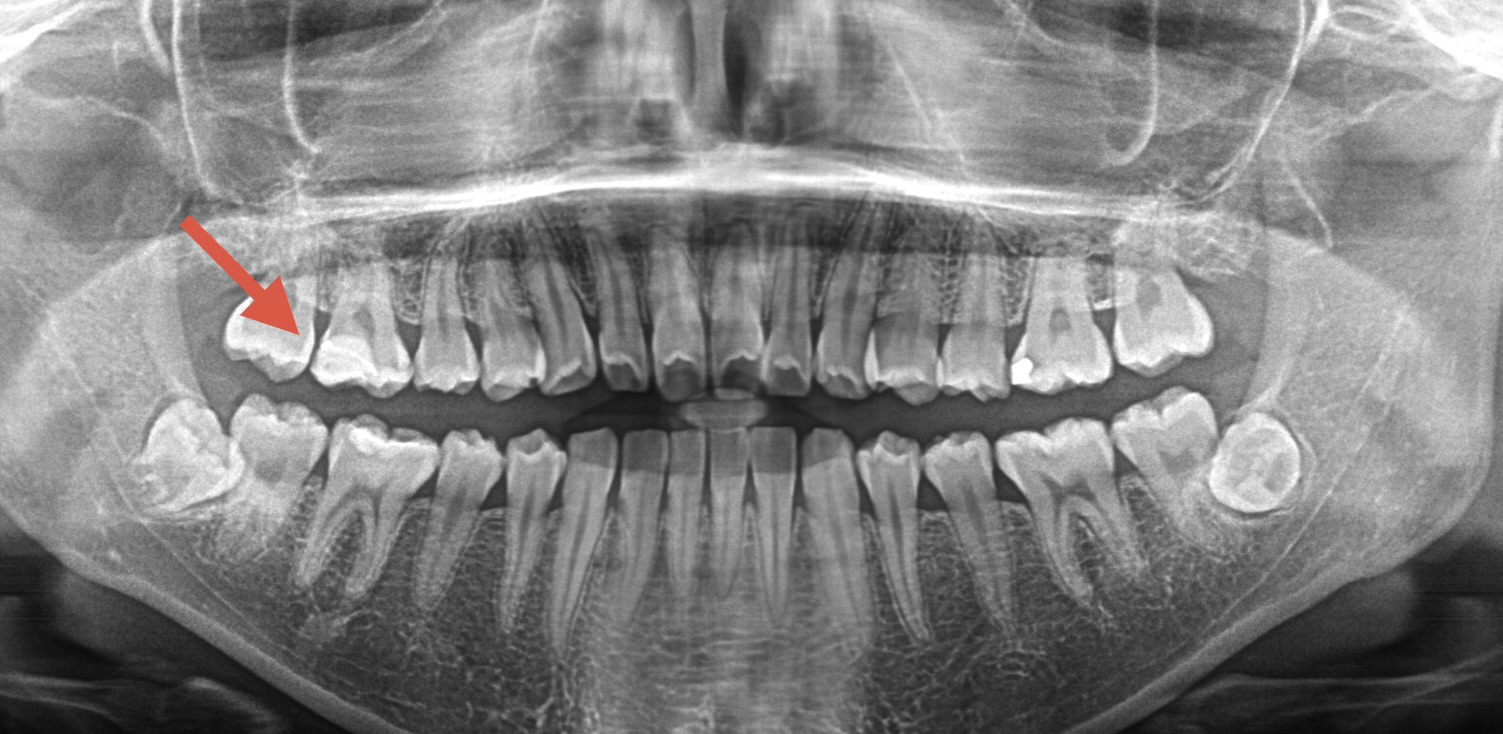

今回は右上第二大臼歯の歯で、昔に治療をされたプラスチックが2次虫歯になりMTAセメントで治療されたケースになります。

治療前の写真がこちらになります。↓ ↓

中では虫歯がかなり大きくあることが次の画像からお分かりいただると思われます。